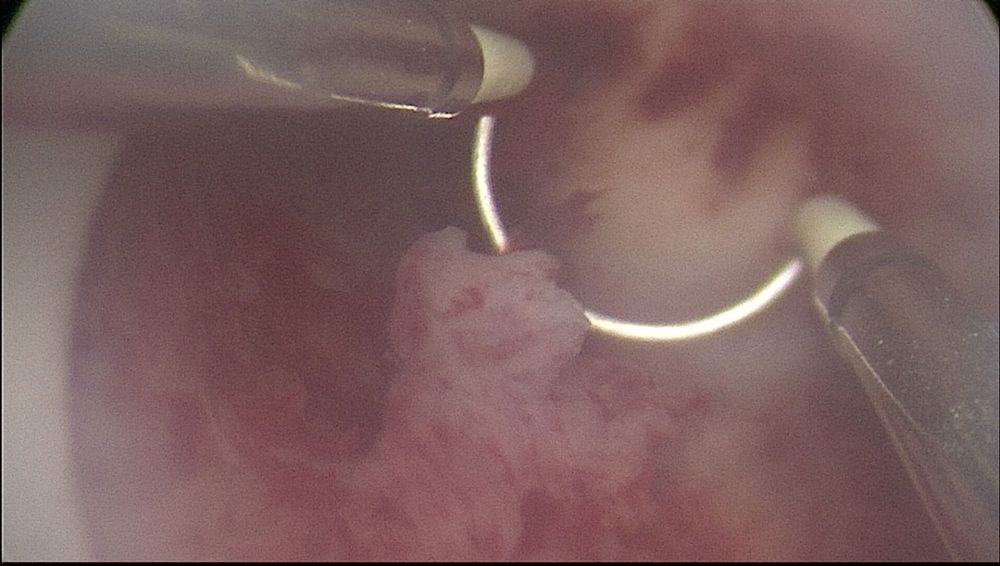

вот такое у меня нашли не понимаю как на узи не видели

вот такое у меня нашли не понимаю как на узи не видели

вот такое у меня нашли не понимаю как на узи не видели

вот такое у меня нашли не понимаю как на узи не видели

Юлия , такие полип сказали бывают не совсем от стимулиции. На стимуляции растут жилестые. А это жилестофиброзный. Тоесть наоборот не на повышение эстроген растёт а на понижение. Ну видимо всё вместе повлияло. Плюс от эндометрит может вырасти. Ещё после выкидыш бывают.